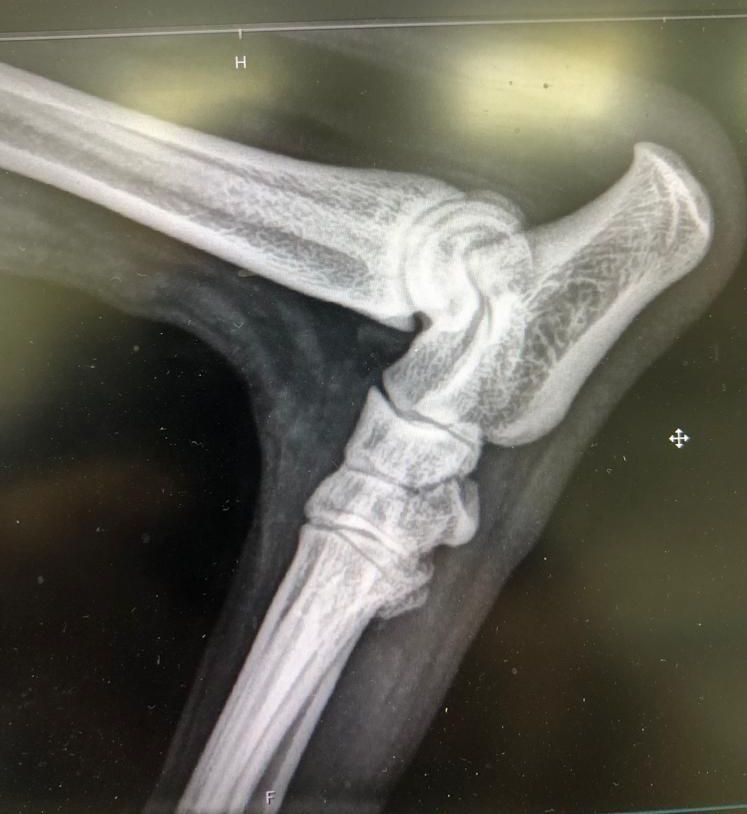

Chirurgie orthopédique

- Le traitement des fractures (simples et compliquées).

- Le traitement de la rupture du ligament croisé.

- Les problèmes d'instabilité de la rotule.

- Les corrections angulaires.

- La prise en charge de la dysplasie du coude ou de la dysplasie de hanches